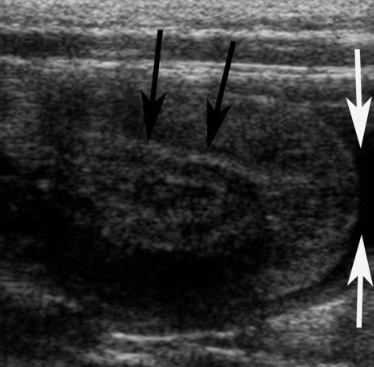

이 고양이는 생후 4개월에 혈뇨, 배뇨곤란, 부적절한 배뇨 증상으로 처음 내원하여 요로감염으로 치료받았습니다. 이후 2개월 뒤 비슷한 임상 증상으로 다시 내원했습니다. 복부 초음파 검사 결과, 방광의 머리 쪽 부위에 2.2 x 2.2 x 1.4 cm 크기의 다층 종괴가 발견되었습니다. 특이하게도, 방광의 머리 쪽 꼭대기 부분이 뭉툭해지고 중앙부가 함몰되어 있었습니다. 바깥쪽의 고에코성 장막층은 함몰된 지점에서 아래쪽으로 종괴의 중심부까지 이어져 있었습니다(그림 17, 18). 컬러 도플러 초음파를 사용하여 종괴 내 혈류가 있음을 확인했습니다. 무에코성 소변이 종괴 바로 아래쪽 방광 내강에서 관찰되었습니다. 초음파 소견을 바탕으로 방광 내번증으로 추정 진단이 내려졌고, 이후 방광 절개술을 통해 확진되었습니다. 내번된 조직을 제거하기 위한 부분 방광 절제술과 동반된 요로감염에 대한 항생제 치료 후 모든 임상 증상이 호전되었습니다.